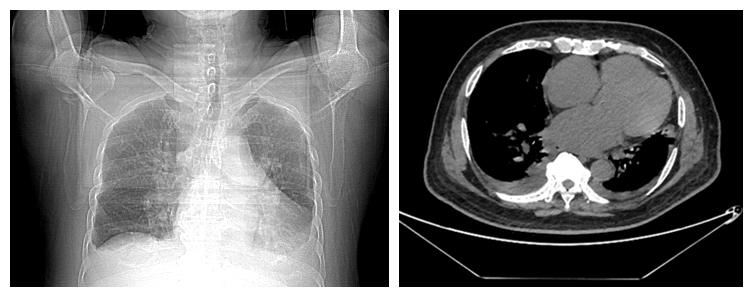

面对KONG先生的危重病情,医护团队立即启动应急流程。迅速建立静脉通路、严密监测生命体征,为后续治疗打开通道。同步进行的肾功能、电解质、胸部CT等关键检查,快速揭示了病情的全貌:肾脏严重损伤、电解质紊乱威胁心脏,心衰已导致肺水肿。这些及时的评估,为制定抢救方案赢得了宝贵时间。

(胸部CT可见全心增大,胸腔积液)